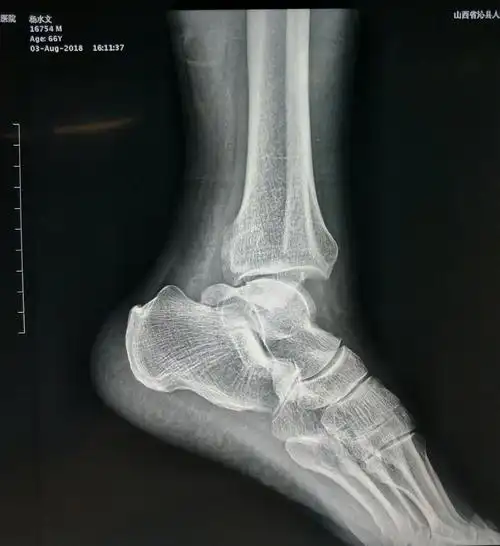

第一次整复双踝骨折大家帮看看

踝关节骨折.楼梯湿滑导致踝关节旋前~外旋四度损伤,下胫腓分离 - 抖音

踝关节骨折伴距骨外脱位非手术治疗

左侧踝关节骨折ser4

踝部骨折一例